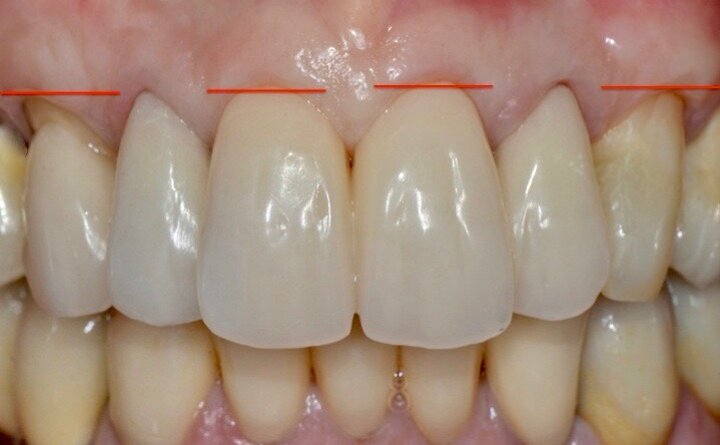

Valutiamo di aver raggiunto una buona simmetria delle parabole gengivali per cui si può procedere con la finalizzazione protesica (Fig. 20). I monconi sono stati preparati con una preparazione verticale per dare priorità alla robustezza dei monconi stessi nella zona cervicale (Figg. 21, 22).

La successiva prova clinica è quella delle ceramiche a biscotto durante la quale viene valutata l’occlusione, la fonetica e l’estetica (Figg. 30-33). Durante la stessa seduta viene eseguita la preparazione per la faccetta in disilicato di litio per il canino superiore sinistro che viene rilevata insieme con l’impronta di rimontaggio delle corone superiori. Una faccetta in resina sul canino viene ribasata e solidarizzata al provvisorio superiore (Figg. 34). La settimana successiva i manufatti finiti vengono provati, cementati adesivamente e vengono eseguite le radiografie finali di controllo (Figg. 35-47).